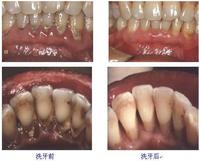

洗牙前后